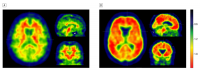

Most current approaches to Alzheimer’s disease focus on the accumulation of amyloid plaque in the brain. The researchers at the Taub Institute for Research on Alzheimer’s Disease and the Aging Brain, led by Adam M. Brickman, PhD, assistant professor of neuropsychology, examined the additional contribution of small-vessel cerebrovascular disease, which they visualized as white matter hyperintensities (WMHs).

The study included 20 subjects with clinically defined Alzheimer’s disease, 59 subjects with mild cognitive impairment, and 21 normal control subjects. Using data from the Alzheimer’s Disease Neuroimaging Initiative public database, the researchers found that amyloid and WHMs were equally associated with an Alzheimer’s diagnosis. Amyloid and WMHs were also equally predictive of which subjects with mildcognitive impairment would go on to develop Alzheimer’s. Among those with significant amyloid, WMHs were more prevalent in those with Alzheimer’s than in normal control subjects.